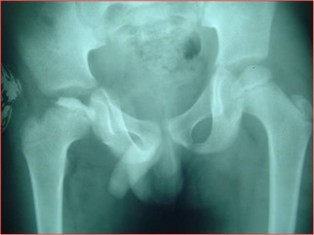

Diagnosing Perthes Disease involves a combination of clinical evaluation, medical history assessment, and imaging studies. X-rays and MRI scans are commonly used to confirm the diagnosis and determine the extent of bone damage.

Perthes Disease, also known as Legg-Calvé-Perthes Disease, is a rare childhood condition that affects the hip joint. It occurs when there is an interruption in the blood supply to the ball-shaped head of the thigh bone (femur), leading to the deterioration of the bone tissue. This can result in pain, limited mobility, and other hip-related issues in children..